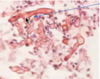

Histoplasmosis

is endemic where

who can get infected by it?

How does is spread?

● Endemic in fertile river valleys

‐ Seen in people who spend a lot of time outside; near Ohio and Mississippi rivers

● Bird and bat excrement

● Airborne spores enter lungs through inhalation

● Macrophage ingests fungusàT‐lymphocyte immunity

● Antibodies develop several weeks later

● Macrophages may confine fungus (express disease later)